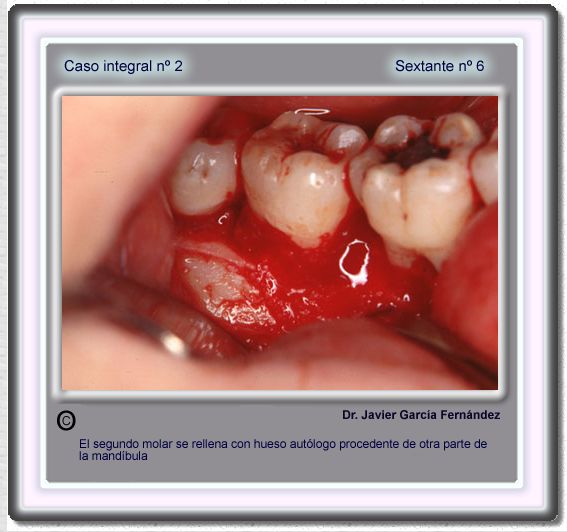

image 79